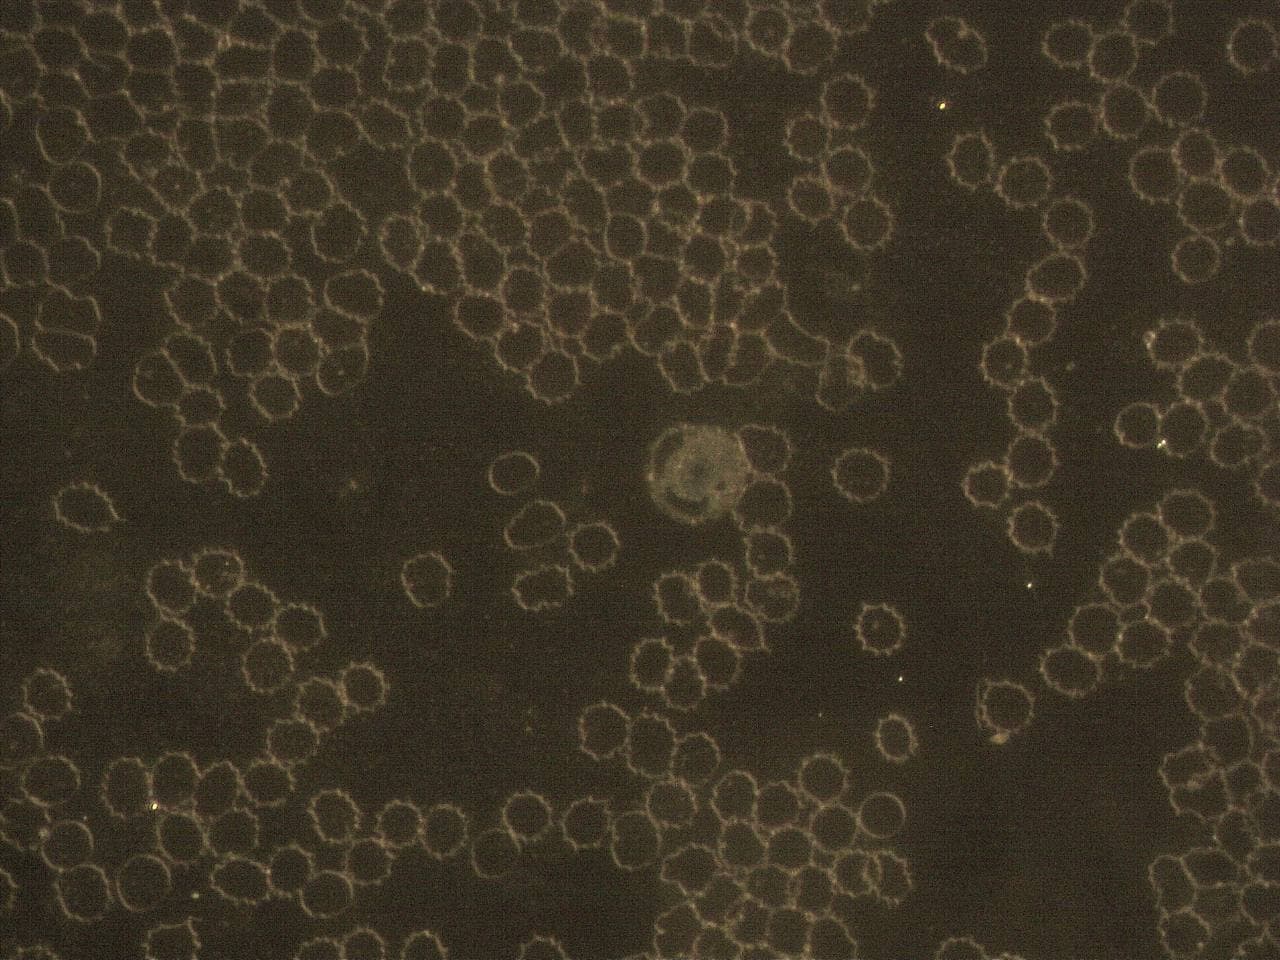

GENimpfschaden

Impfschäden Schweiz Coronaimpfung, [15.09.21

https://t.me/Impfschaden_Corona_Schweiz/21523

Scheibenartige Form mit Spike Proteinen (?)

GENimpfschaden im Blutbild 15.9.2021: Foto 2

GENimpfschaden

Impfschäden Schweiz Coronaimpfung, [15.09.21

https://t.me/Impfschaden_Corona_Schweiz/21524

Seltsame Form über den Erys

GENimpfschaden im Blutbild 15.9.2021: Foto 3